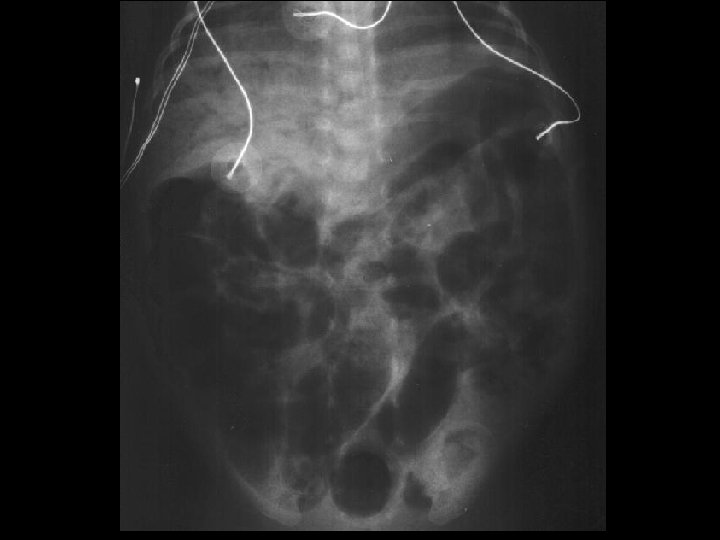

Case 2 Radiology Evaluation • Upper GI – Flow through normal duodenum, duodenal-jejunal junction, jejunum • Contrast enema – Microcolon – Distended RUQ loops do not fill during enema • Small bowel follow-through – Opacification of distended loops Jose Chavez CHO MR 960117

Case 2 Radiology Diagnosis • Microcolon • Dilated ileum secondary to obstruction • Differential diagnosis: – Stricture – Adhesions – Meconium Ileus Jose Chavez CHO MR 960117

Case 2 Surgery • Exploratory laparotomy • Extensive lysis of adhesions • Resection of 11 cm of distal ileum secondary to a concealed perforation • Creation of a double-barrel ileostomy Jose Chavez CHO MR 960117

Case 2 Findings at Surgery “Most of the small bowel in the proximal part of the jejunum all the way to the distal jejunum was quite small, and so was the ascending, descending colon. The distal small bowel appeared very distended and there was a lot of adhesions in the right lower quadrant involving several loops of distal ileum. It was apparent that there was a concealed perforation involving a segment of the distal ileum causing a significant amount of inflammatory changes and adhesions, which is causing the bowel obstruction. ” Jose Chavez CHO MR 960117